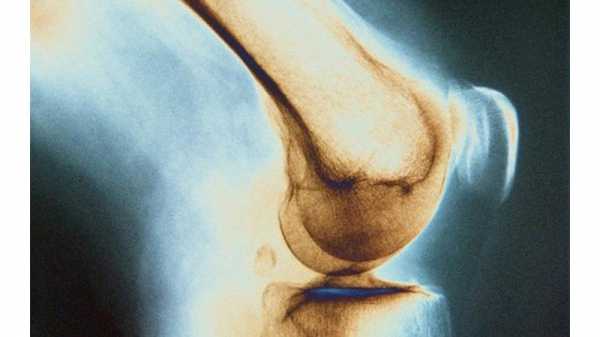

Рентген

С помощью рентгеновских лучей можно выявить наличие множества заболеваний, которые нельзя заметить невооруженным глазом. При этом такой диагностический метод не имеет болевых ощущений и доступен по своей стоимости. На сделанном снимке пораженные участки костей видны, как темноватые пятна, а ещё можно наблюдать увеличивающееся расстояние между суставами, а также их сращение. Внутри костей может быть видно истончение или полостные образования, ткани могут быть подвергнуты абсцессу, как правило это наблюдается вокруг больной кости.

Как диагностируется заболевание

Все пациенты при подозрении на костный туберкулез проходят рентгенографию или томографию пораженного органа в двух проекциях. При этом следует определить очаг костного разрушения (секвестры) и тени от абсцессов.

Признаки болезни можно увидеть на рентгеновских снимках. Между суставами появляются расстояния, изменяется костная структура, поверхность хрящей становится неровной, в кости появляются полости. Пораженные суставы можно определить по наличию припухлостей тканей или их атрофии.

Рентгеновские лучи уже много лет позволяют диагностировать много болезней, которые не видимы для глаза. Метод диагностики не сопровождается болевыми ощущениями и является доступным.

На рентгеновском снимке пораженные костные участки видны как темные пятна. Можно увидеть изменение расстояния между суставами или их сращение.

Выявляется истончение или образование внутрикостных полостей, наличие абсцессов в тканях, вокруг пораженной кости.

Для диагностики туберкулеза костей применяется рентгенологическое исследование легких и пораженного отдела скелета. На фото рентгена хорошо просматриваются такие костные изменения, как сужение суставных щелей, неровные поверхности хрящей, размытость очертаний поврежденных костей, образование полостей, расслоение межмышечных промежутков, вызванное отеком. Туберкулезный абсцесс проецируется в виде тени около очага поражения.